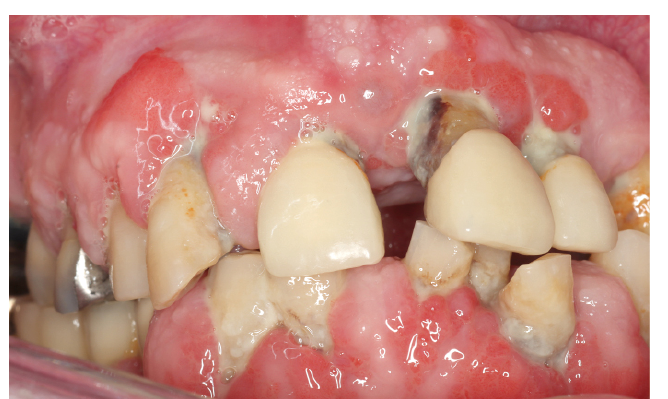

Menschen mit Diabetes sind chronisch krank, oftmals mehrfach mediziert, haben Komorbiditäten und sind dadurch, wie viele andere Risikopatientengruppen, in einer festen Rolle („chronisch krank“). Dabei geraten bei chronisch Allgemeinerkrankten oftmals mundgesundheitsbezogene Themen nicht nur in den Hintergrund, sondern werden vielmehr auch als nicht mehr relevant empfunden. Dieser Prozess verläuft langsam und kann als Response shift beschrieben werden (34). Demnach besteht in der Patientenperspektive nicht nur oftmals kein Handlungsdruck für einen Besuch in der Zahnarztpraxis, sondern auch kein subjektiver Mehrgewinn einer zahnmedizinischen Betreuung. Dies wird insbesondere dadurch erschwert, als dass oftmals auch ein „negatives Feedback“ durch das zahnmedizinische Team erfolgt (Änderung der Mundhygienemaßnahmen erforderlich – Mehrbelastung des Betroffenen – Verstärkung des Response shift/Reaktanz, Abb. 3). Im Extremfall kann der Response shift zum völligen Neglect in Bezug auf die Mundgesundheit führen, wie der Fall in Abbildung 4 illustriert.